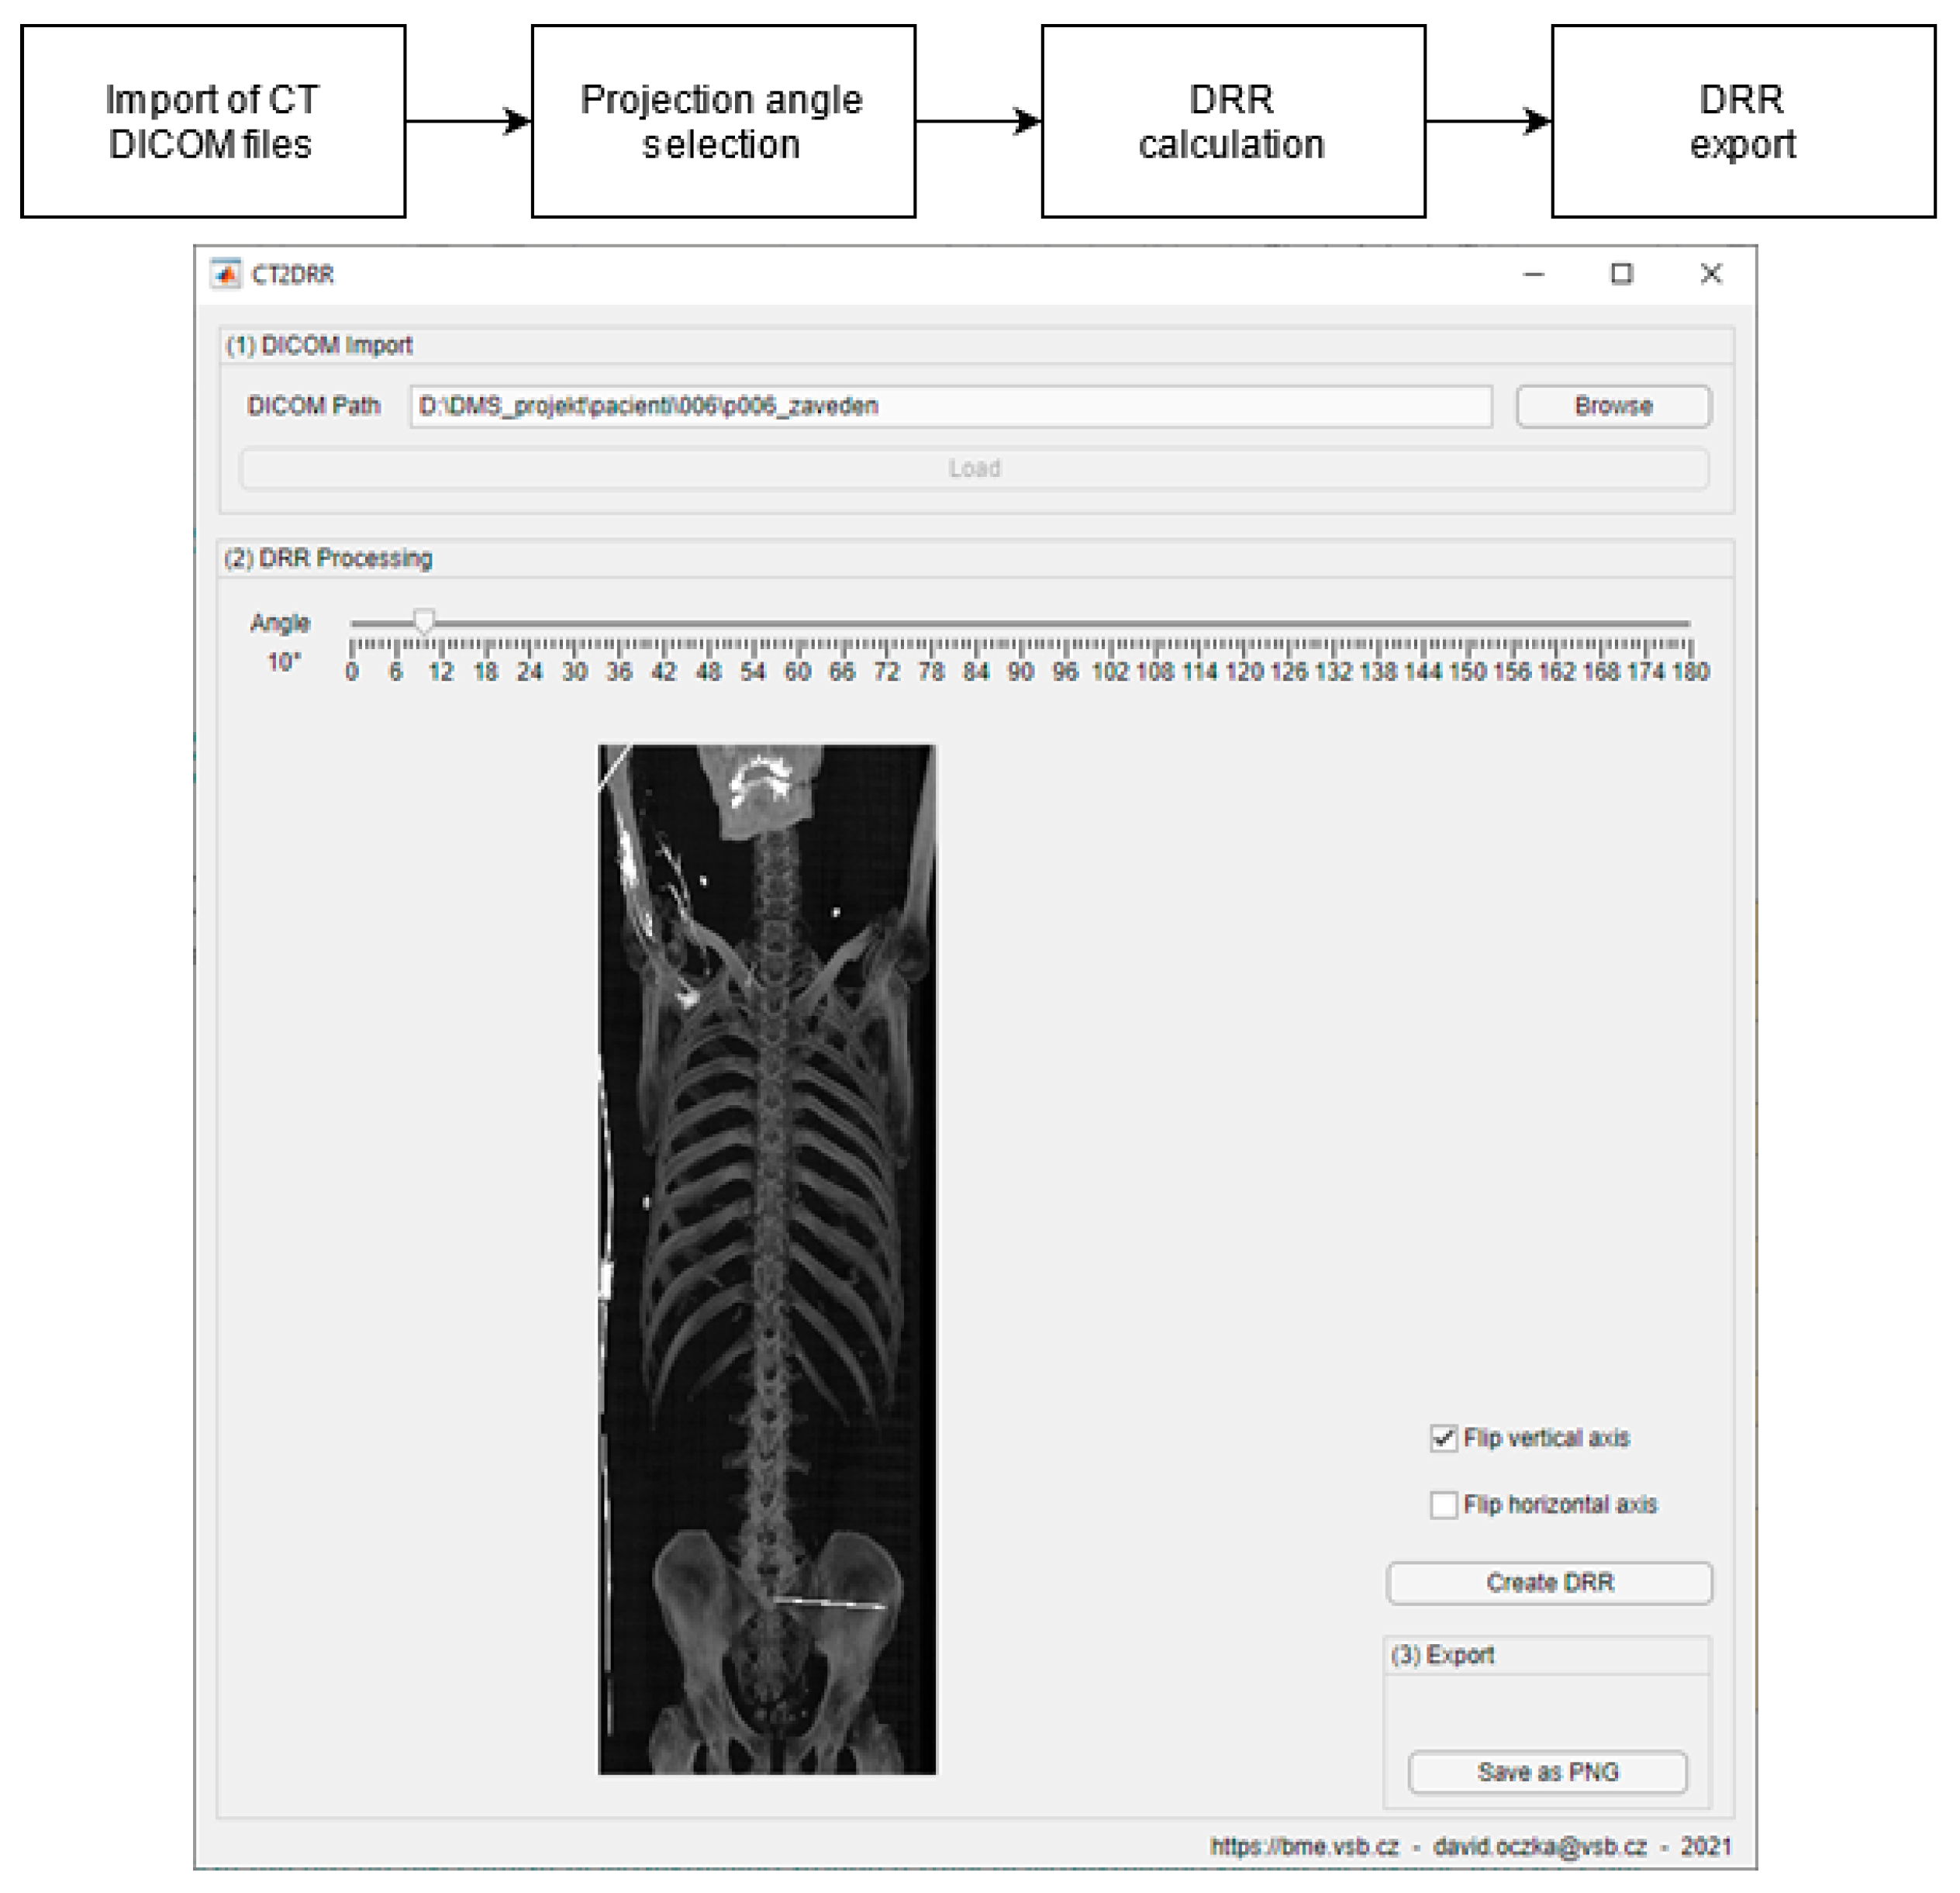

- Generation of digitally reconstructed radiograph (DRR) projections

3.2. DDR Projection Generation (CT2DDR)